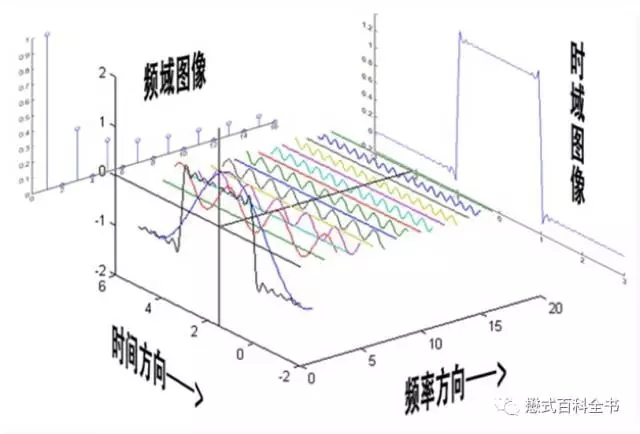

图1:这个图是网上找的一个比较直观的反映傅里叶变换的图

时间域函数简单来说就是以函数来描述随着时间变化,目标(信号强度,幅度.....)的变化的关系。

频率域函数就是以函数来描述目标频率。

图2:图解傅里叶变换FT,上面为一个时间域函数,随时时间变化,信号的变化函数;下图为一个频率域函数,表示经过傅里叶变换后,该信号的频率。本例中可以看到,上面的信号随着时间变化呈周期性变化,信号形状不是标准的正弦曲线和余弦曲线,说明信号包含两种以上不同频率,经过FT后,把信号的频率分解出来。